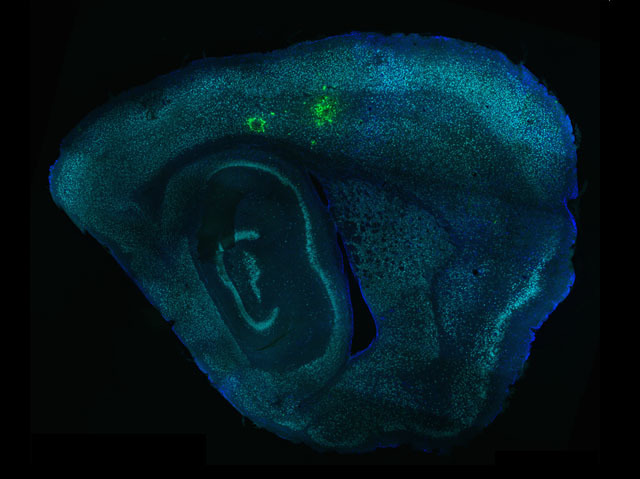

Toxoplasmosis, caused by the parasite Toxoplasma gondii, is a disease that affects the brain and occurs in humans mainly as a result of eating parasite-infected meat or from contact with infected cats’ faeces. It doesn’t usually cause symptoms in healthy adults but for people with a weak immune system it can lead to life-threatening brain infections. Because laboratory experiments on isolated cells can’t accurately show the interaction with Toxoplasma, an innovative technique has been developed to track which brain cells the parasite invades in whole tissue. By engineering Toxoplasma to inject a molecule (Cre) into the cells it infects, scientists were able to see in a section of mouse brain (pictured) that the parasite prefers to interact with neurons (green fluorescence showing Cre) rather than astrocytes, another type of brain cell. This preference may be determined by the size and width of the neurons compared to other brain cells.